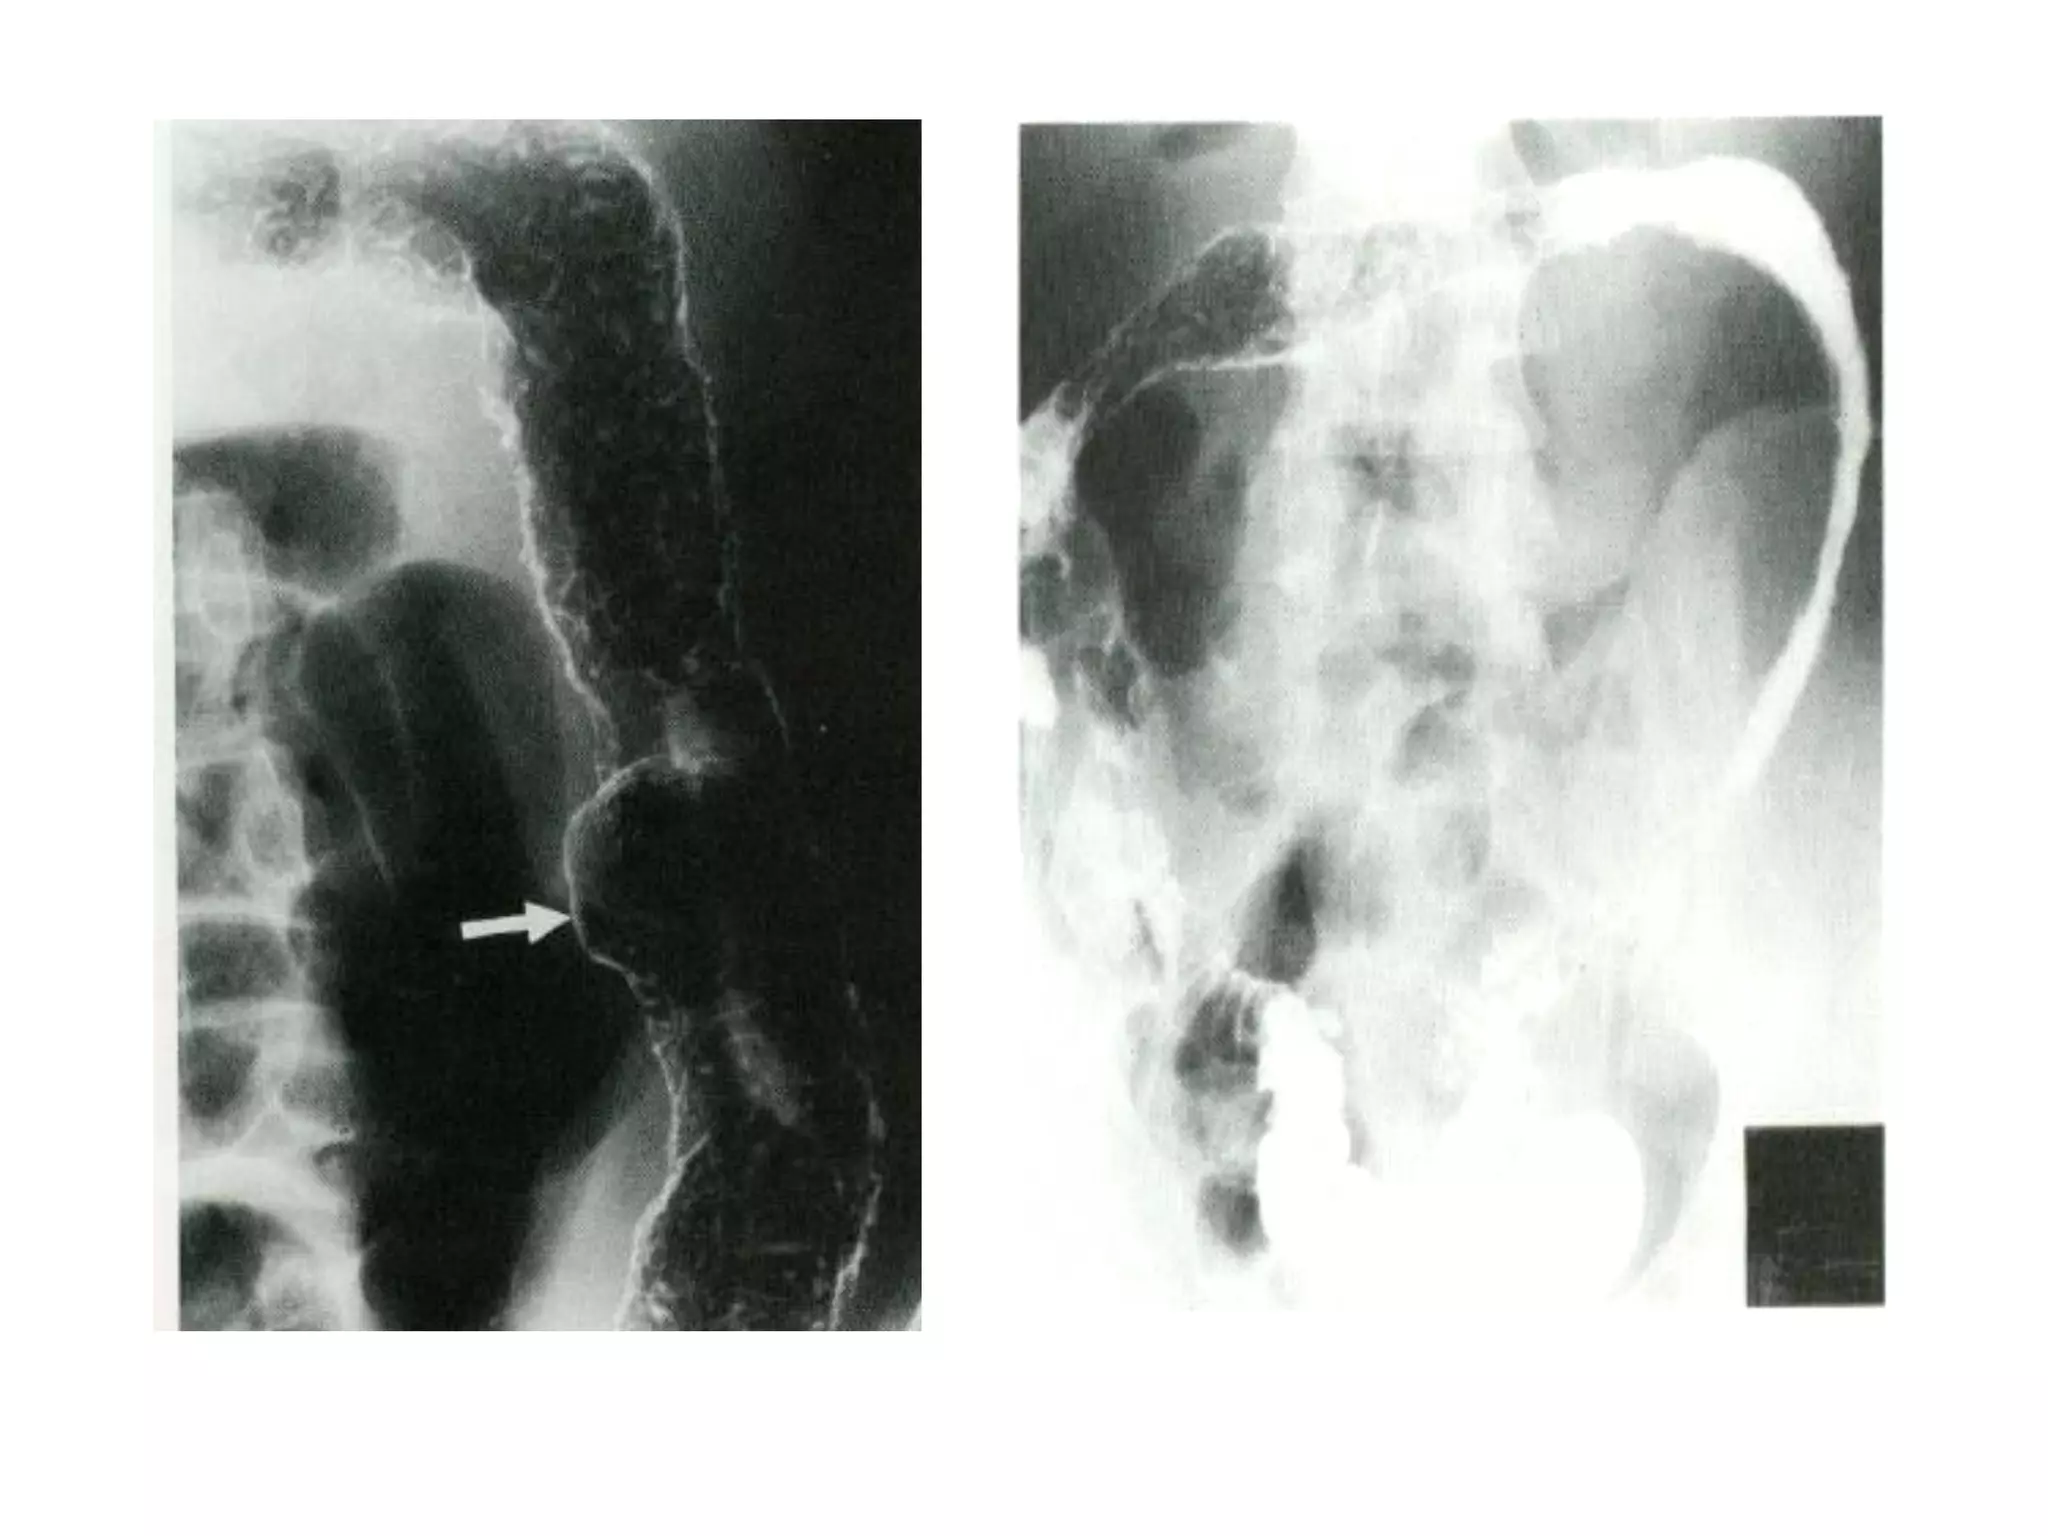

2. Nội soi

Tổn thương NGẮT QUÃNG & KHÔNG ĐỐI XỨNG

Hình ảnh đại thể nổi bật:

• Loét dạng đường

• Dạng lát đá (cobberstone)

• Dày thành ruột và hẹp lòng ruột

• Hình thành đường dò

37

CROHN

NỘI SOI

Tiến triển không đều như UC, nhìn chung gồm 3 GĐ

Sớm nhất là loét rải rác dạng áp-tơ (nông), xung

quanh là niêm mạc bình thường

Loét tăng số lượng & kích thước, tình trạng phù nề

của lớp dưới niêm tạo ra hình ảnh lát đá điển hình

Giai đoạn sau: thành ruột dày lên và lòng ruột hẹp

lại do hiện tượng xơ hóa.